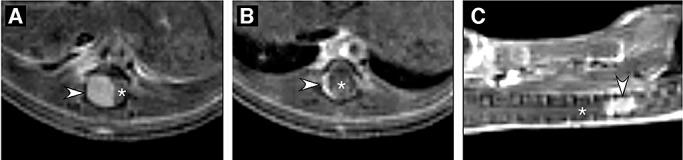

Meningiomas account for approximately 30% of all primary central nervous system tumors and are found in half of neurofibromatosis type 2 patients often causing significant morbidity. Although most meningiomas are benign, 10% are classified as atypical or anaplastic, displaying aggressive clinical behavior. Biallelic inactivation of the neurofibromatosis 2 (NF2) tumor suppressor is associated with meningioma formation in all NF2 patients and 60% of sporadic meningiomas. Deletion of the p16(INK4a)/p14(ARF) locus is found in both benign and malignant meningiomas, while mutation of the p53 tumor suppressor gene is uncommon. Previously, we inactivated Nf2 in homozygous conditional knockout mice by adenoviral Cre delivery and showed that Nf2 loss in arachnoid cells is rate-limiting for meningioma formation. Here, we report that additional nullizygosity for p16(Ink4a) increases the frequency of meningioma and meningothelial proliferation in these mice without modifying the tumor grade. In addition, by using magnetic resonance imaging (MRI) to screen a large cohort of mutant mice, we were able to detect meningothelial proliferation and meningioma development opening the way to future studies in which therapeutic interventions can be tested as preclinical assessment of their potential clinical application.